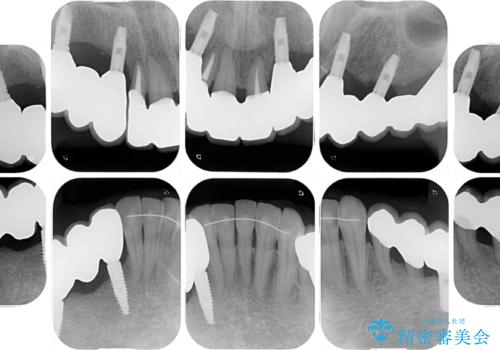

歯を抜かないといけない部分はインプラントとオールセラミッククラウンにより咬合を回復させ、歯周外科処置を行う歯については、同じくオールセラミッククラウンにて補綴治療を行うこととしました。

外科処置を多く行ったため、その待ち時間が長くかかり、さらには途中矯正治療も行なったので、治療期間は長期間となりました。